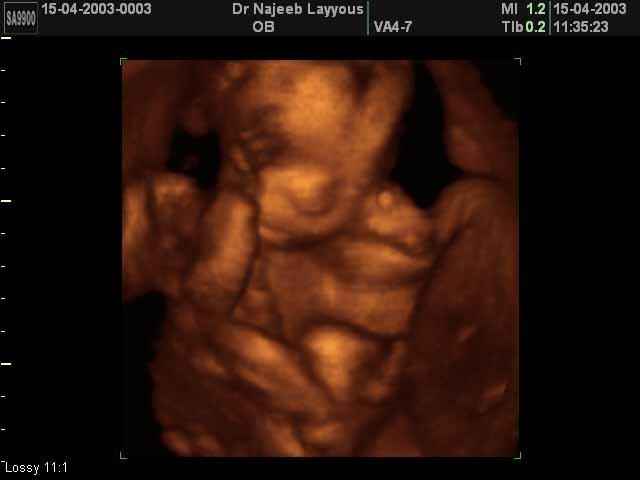

- Fetal Behavior Ultrasound Photos

Ultrasound Photos in 3D showing Fetal Behavior Inside the uterus | Dr N Layyous